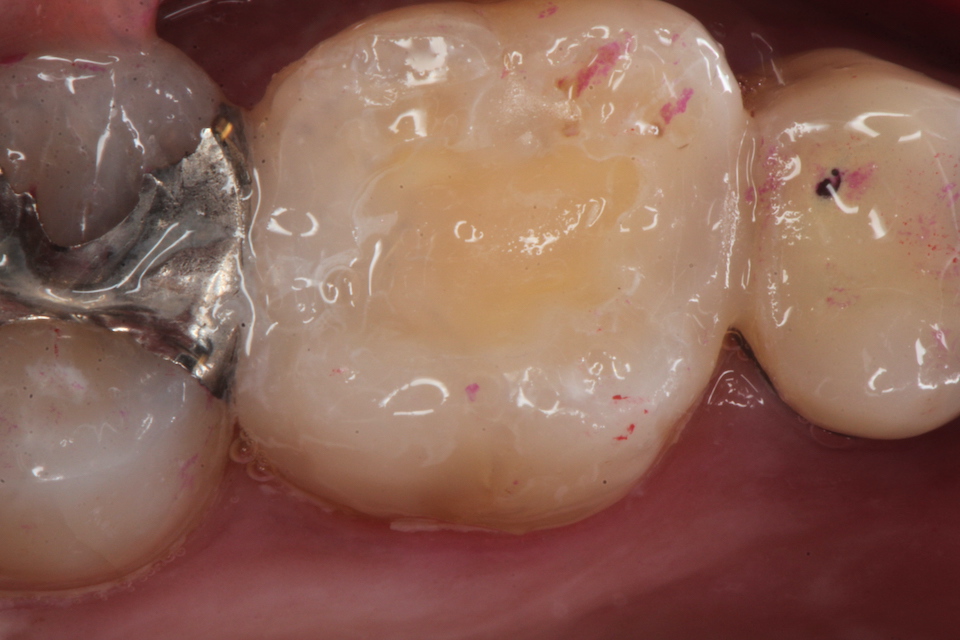

残根上のCR(ダイレクトボンディング)8 2025.11.12

ブリッジ脱離で2次カリエス+Perでグラグ… 2025.11.01

ブリッジ脱離で2次カリエス+Perでグラグ… 2025.10.31